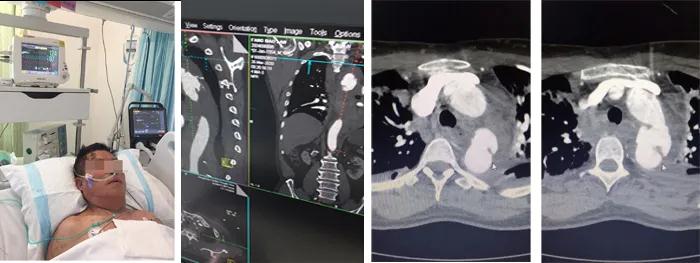

3月26日,66歲的房先生因為車禍事故導致全身多發(fā)骨折,生命體征不穩(wěn)定,在當?shù)蒯t(yī)院診斷為多發(fā)肋骨骨折、雙肺挫傷、左側(cè)血胸、創(chuàng)傷性失血性休克,CT影像檢查發(fā)現(xiàn)可疑主動脈夾層。因病情嚴重緊急,迅速轉(zhuǎn)運至我院急診科,經(jīng)創(chuàng)傷救治綠色通道CT室急診行主動脈CTA檢查,示降主動脈夾層破裂,縱膈及左側(cè)胸腔大量積血,右側(cè)血氣胸。急診收入我院心臟大血管外科。

入院后,患者呼吸微弱,血壓僅65/40mmHg,血常規(guī)示:血紅蛋白由130下降至49g/L。主動脈CTA確診患者為主動脈夾層破裂,主動脈內(nèi)膜撕裂形成假性動脈瘤,胸腔和縱膈出現(xiàn)大量積血。柴召強醫(yī)師考慮患者病情患者危重,休克狀態(tài),隨時有死亡可能。向醫(yī)務(wù)部周永勤主任匯報,并向患者家屬講明病情,決定急診行主動脈腔內(nèi)覆膜支架植入腔內(nèi)修復(fù)術(shù)。

患者術(shù)后帶氣管插管轉(zhuǎn)入ICU,予輸血、補液、抗休克、預(yù)防感染治療。由于外傷嚴重,加上重癥肺挫傷,患者一度出現(xiàn)呼吸衰竭綜合征(ARDS),在重癥醫(yī)學科與心臟大血管外科醫(yī)護人員7天7夜的嚴密守護下,患者闖過了呼吸衰竭關(guān),情況趨于穩(wěn)定。后轉(zhuǎn)入普通病房,目前患者已康復(fù)出院。